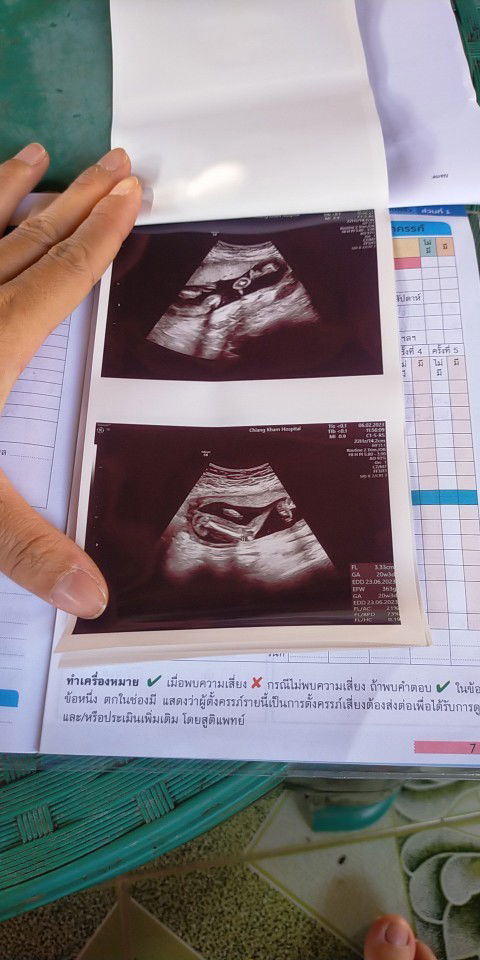

เมื่อวานแม่บ้านนี้ไปหาหมอมา หมอบอกน้องน่าจะเป็นผู้หญิง แม่ก็แอบดีใจเพราะอยากได้ผู้หญิง เพราะทางบ้านแฟนมีแต่หลายผู้ชาย ขอให้เป็นผู้หญิงเหมือนที่หมอบอกด้วยนะค่ะ #ทีมลูกสาว กำหนดคลอดเดือนมิ.ยค่ะ แต่แม่ต้องได้ผ่า เพราะท้อง2แม่ได้ผ่าค่ะหมอบอกกลัวมดลูกแตก ทีม มิ.ย.แม่บ้านไหนได้ลูกชายลูกสาวบ้างค่ะ